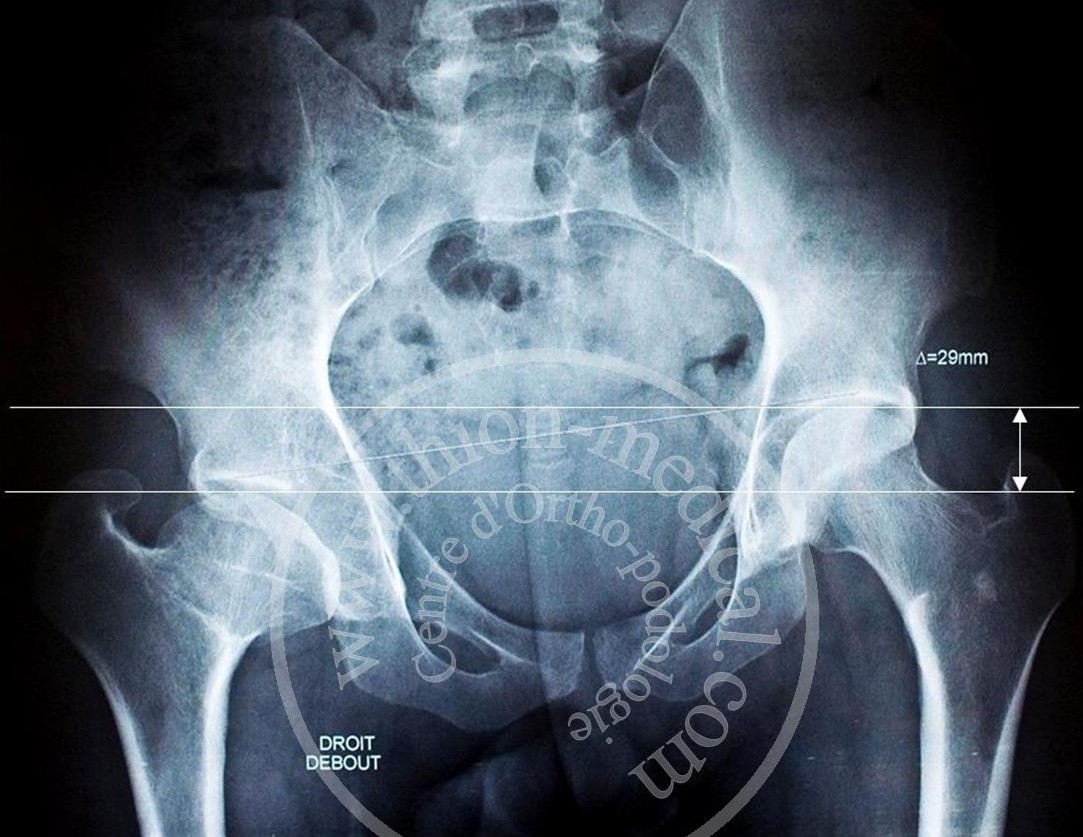

Une Jambe plus courte que l’autre se confirme en prenant une radiographie du bassin de face. On mesure ainsi le déficit en mm, en comparant la différence de hauteur entre les sommets des têtes fémorales droite et gauche.

(Radiographie du bassin)

On remarque que le bassin est déséquilibré, c’est-à-dire qu’il est incliné soit vers la droite ou soit vers la gauche. La colonne vertébrale qui est planté sur le sacrum amorce, dans le plan frontal, une courbure au niveau des vertèbres lombaires compensée plus haut par une autre courbure opposée. C’est la signature d’une attitude scoliotique ou d’une vraie scoliose. La scoliose implique une rotation des corps vertébraux qui amorce une gibbosité. Cette ILMI peut être acquise, due à un problème au niveau des cartilages de croissance suite à un traumatisme (choc, fracture) ou à une perturbation de la vascularisation des segments articulaires ou encore une maladie infectieuse ou neurologique.

Un grand nombre de personnes ignorent qu’elles ont une ILMI. En effet, soit le déficit (la différence de hauteur entre les sommets des têtes fémorales droite et gauche) est faible, et l’on peut très bien vivre toute sa vie sans ne jamais ressentir aucune gêne, soit le déficit est plus marqué et les lombalgies ou les douleurs articulaires dans la hanche peuvent se déclenchées beaucoup plus tard.